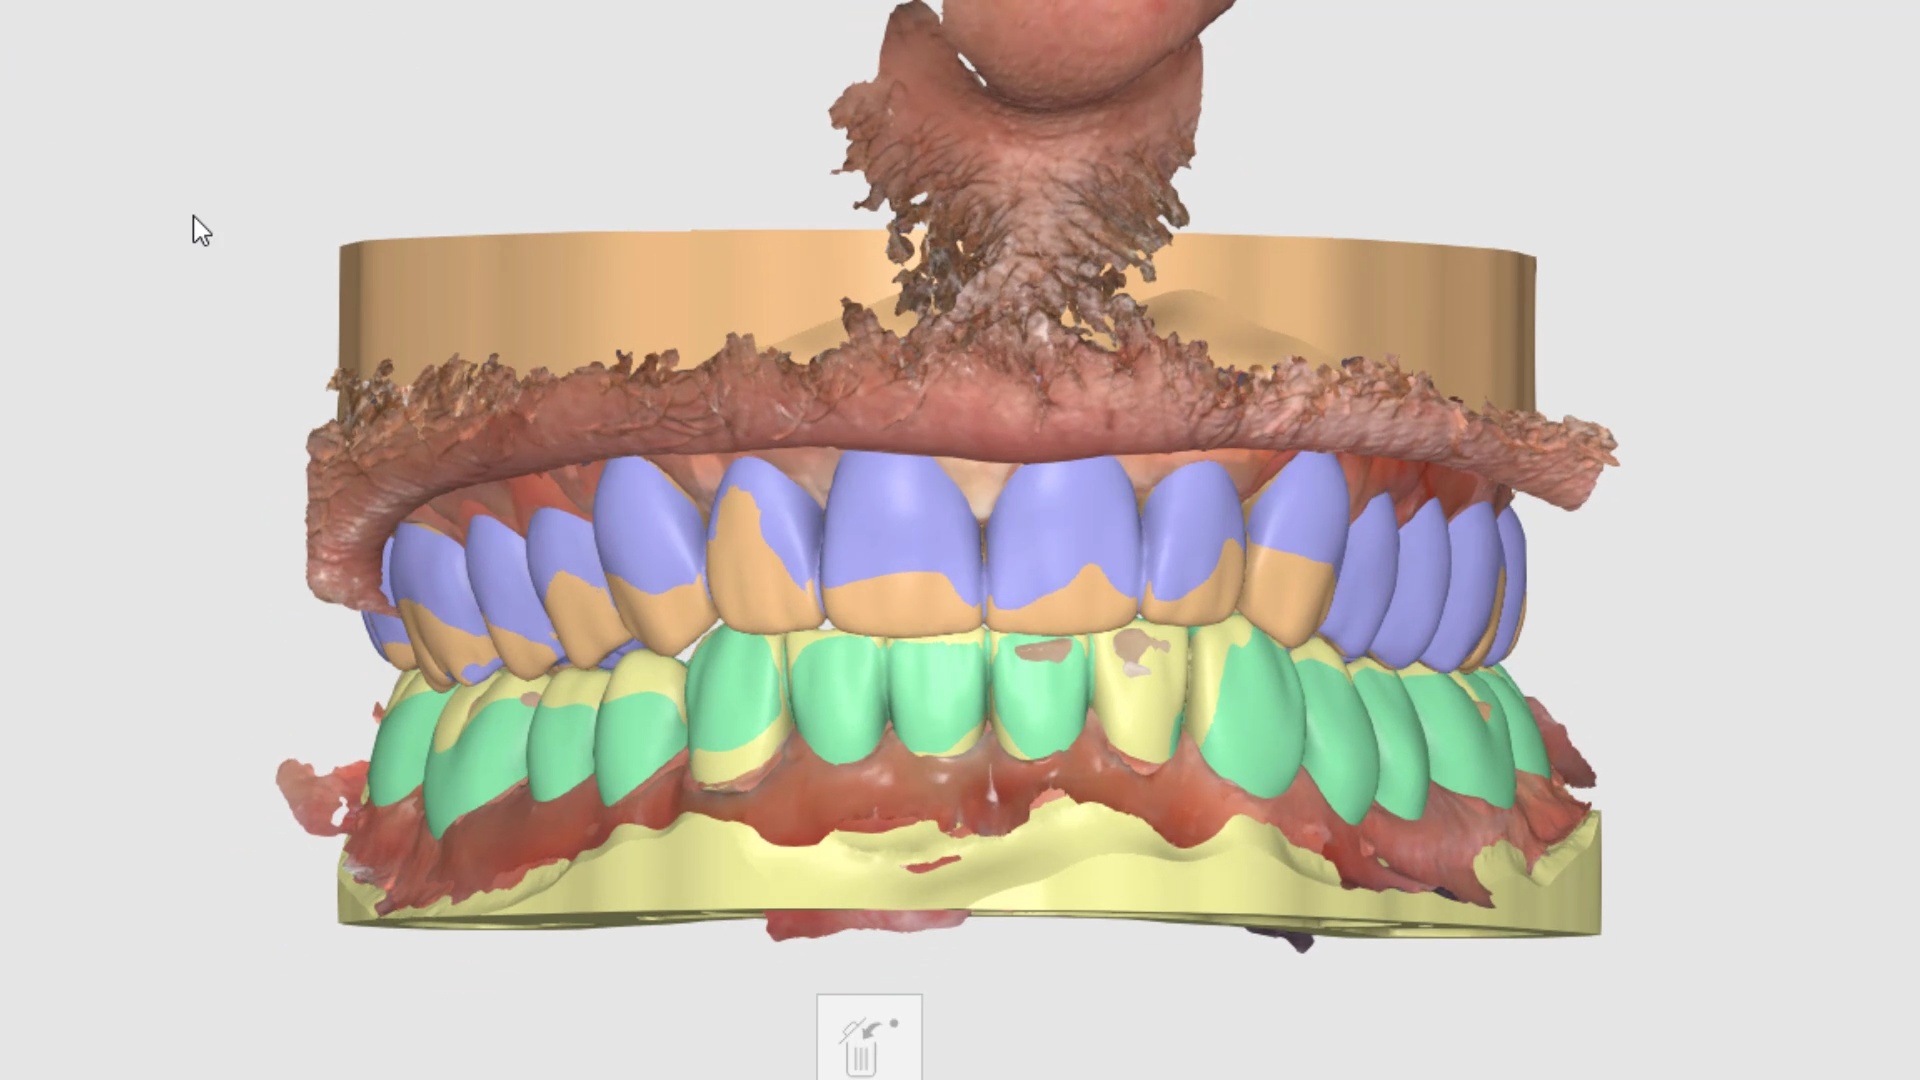

March 17, 2022the patient was sedated and intubated for the case so we could not keep track of the bite. Instead, we imaged all 30 prepared teeth and used medit compare […]

the patient was sedated and intubated for the case so we could not keep track of the bite. Instead, we imaged all 30 prepared teeth and used medit compare […]